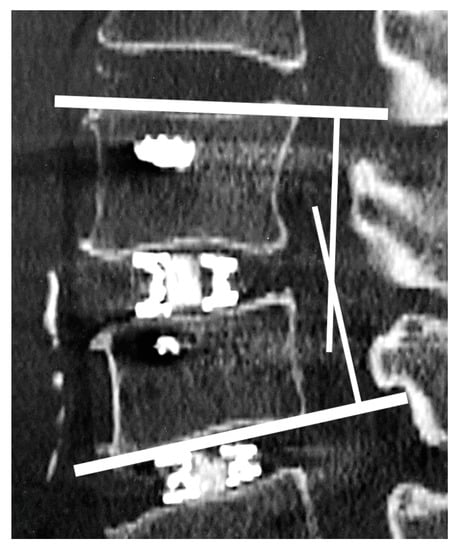

2.5. Vertebral Endplate Concavity (VEC) and Cage Subsidence

VEC was defined as a concavity ≥ 1 mm along the cage or an obvious fracture of the vertebral endplate on first postoperative CT images compared with preoperative CT images. Additionally, VEC was investigated for any increase or change in CT images at three months postoperatively. The Marchi classification was used to assess cage subsidence [] by comparing images immediately postoperatively and three months later on the following scale: grade 0 = 0–24% loss of postoperative disc height, grade I = 25–49%, grade II = 50–74%, and grade III = 75–100% (Figure 5).

Figure 5. Vertebral endplate concavity (VEC) and cage subsidence. Both cages exceeded the end plates by ≥1 mm (VEC-positive) with Marchi classification grade 0.